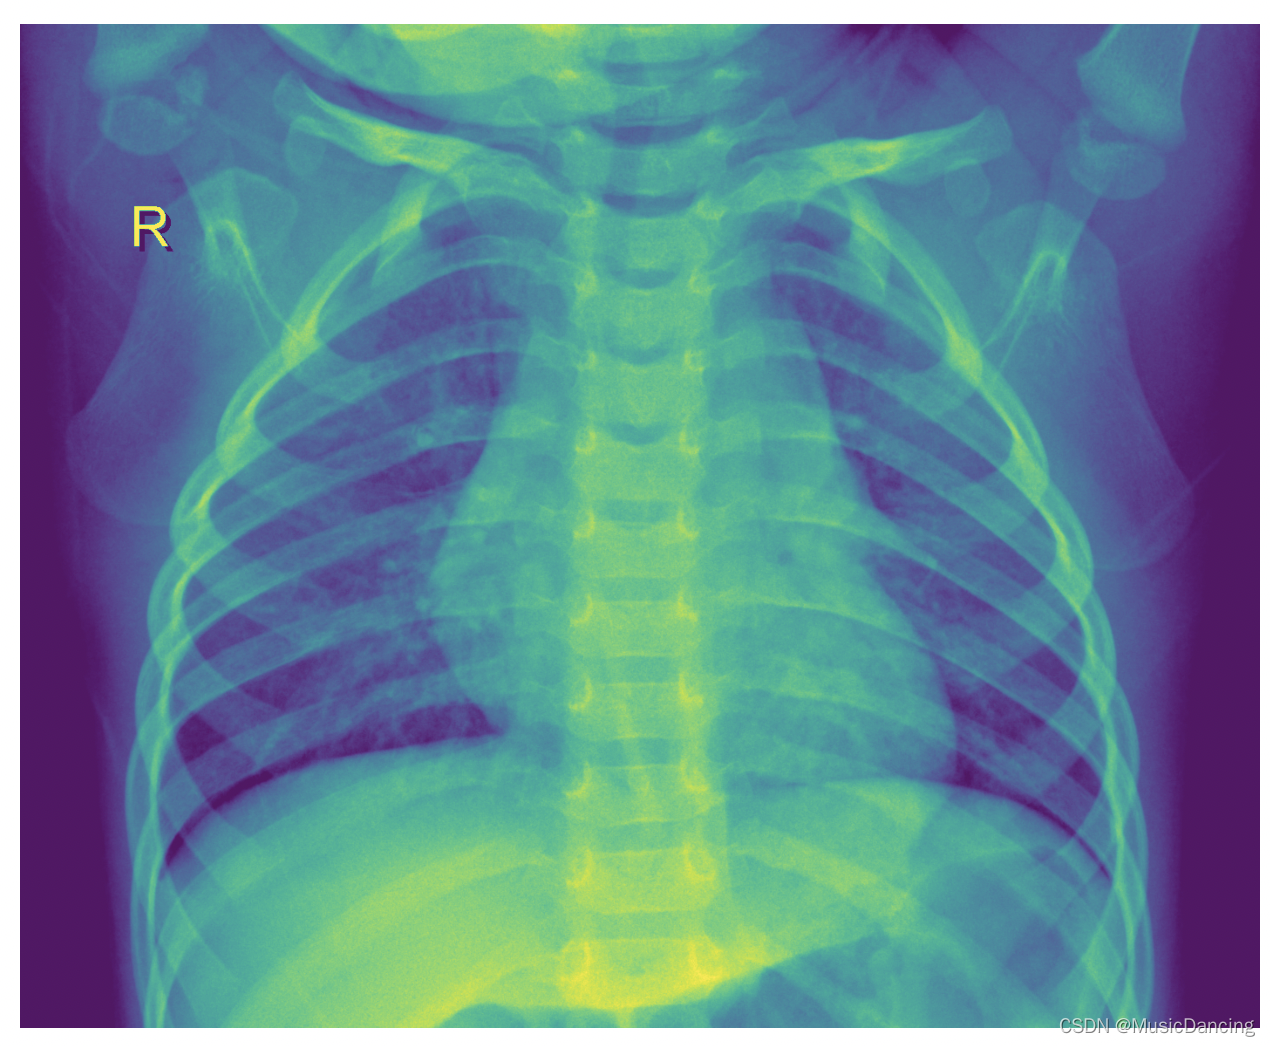

3.2 显示数据集中的图片

参考:https://blog.youkuaiyun.com/MusicDancing/article/details/122107467

3.2.1 绘制图片

从url读取图片